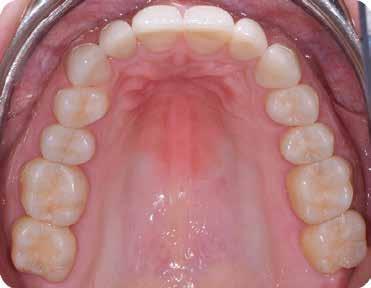

5. Alsó okkluzális (tükör)

Az asszisztens most a kisebb retraktorokat fordított V alakban leengedi, hogy az alsó ajkakat oldalra és a fogaktól távolabb húzza vissza. A klinikus most felfelé

emeli a tükröt, hogy láthatóvá tegye az alsó ív tükörképét, miközben a pácienst arra kéri, hogy „emelje fel kissé az állát”. Ideális esetben a felvétel a tükör síkjához képest 90°-ban készül, úgy, hogy az utolsó jelenlévő zápfog látható legyen. Fontos kérdés lenne itt a páciens nyelvhelyzete a fénykép készítése közben. A legjobb, ha megkérjük a pácienst, hogy „görgesse viszsza” a nyelvét a tükör mögé, hogy az ne zavarja a fogak láthatóságát, különösen a hátsó területen (11. ábra).